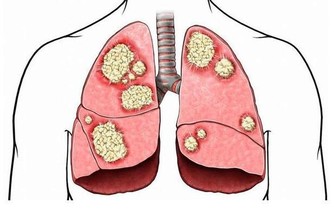

過量飲酒會降低肝臟淨化血液的能力,導致體內毒素增加,誘發肝臟損傷及多種疾病。

另外,酗酒還容易導致肝臟中毒,誘發肝炎。長期過量飲酒則容易導致肝硬化。每天飲高濃度酒超過兩杯(25 毫升)就會傷肝。